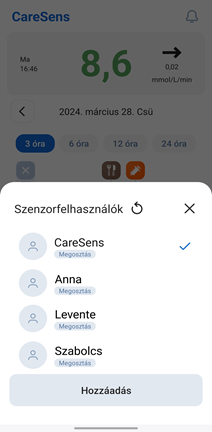

Sens365 alkalmazás

Megoszthatók a diabétesz kezeléséhez szükséges különböző terápiás adatok, cukorértékek és trendek.

* Az alkalmazás képernyője a szoftver verziójától függően eltérhet.